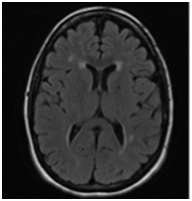

At 34 weeks of gestational age the patient was admitted to the hospital due to severe right eye pressure-like headache associated with transient right upper limb weakness for 24 hours. Her blood pressures were normal and preeclampsia was ruled out. The physical exam performed by the neurologist was significant for mild flattening of right nasolabial fold. There were no other abnormal neurologic or psychiatric findings. The MRI (Figure 1) showed multiple small foci of abnormal signal in the cerebral white matter consistent with micro vascular ischemic changes but no acute pathology. This episode was self-limited and the patient was discharged home in stable condition after 10 days.

• Figure 1 MRI performed at 34.0 weeks of gestation.

The most common lesions seen on MRI occur in the per ventricular and deep white matter. Lesions are initially nodular or punctiform and become diffuse and symmetric. The most suggestive areas affected by CADASIL are the external capsule and anterior temporal lobe. As opposed to multiple sclerosis, basal ganglia and thalamus are also affected. The severity is higher in symptomatic patients and increases dramatically with age.